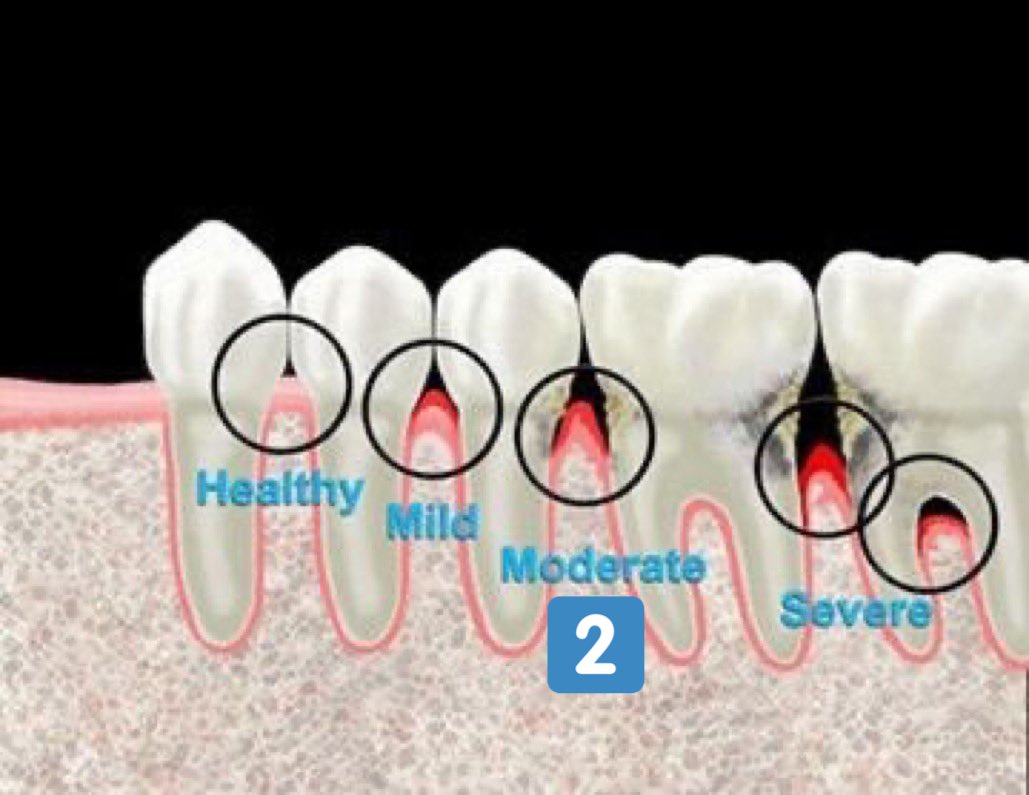

التهاب اللثة العميق(مرحلة٢):

-تآكل بسيط في اطراف العظم الداعم للآسنان وقد(غالبا)يكون مصحوب بعلامات من التهاب اللثة الخارجي

اعراضه قد تشابه المرحلة (١) وقد لا يكون ظاهرا

-يمكن علاجه إذا اكتشف باكرا وإيقاف تقدمه.